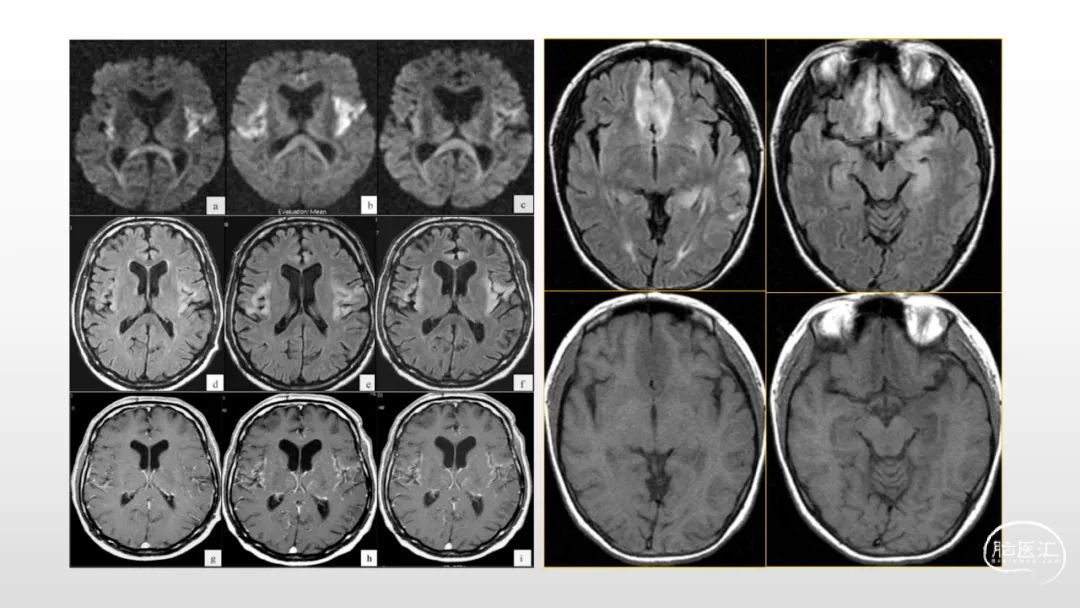

颅脑影像诊断基础知识讲座:感染和免疫性疾病1